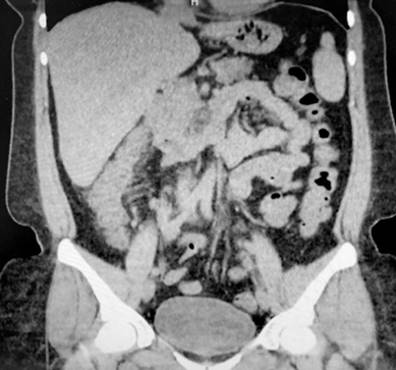

A 43-year-old female patient with a medical history of ankylosing spondylitis (AS) since the age of 20, fibromyalgia, arterial hypertension, hypothyroidism, and latent tuberculosis treated in 2019 presented to the hospital with symptoms of diffuse abdominal pain and multiple bloody diarrheal stools (more than fifteen times a day) for a week. The patient had been treated with etanercept, adalimumab, abatacept, and since 2017, with secukinumab. On admission, the patient was tachycardic, dehydrated, afebrile, and had lower abdominal pain without signs of peritoneal irritation. Laboratory tests showed no alterations in blood count, and an ultrasound and tomographic study revealed wall thickening of the right colon with mucous enhancement, multiple mesenteric lymphadenopathies, and some free fluid at the bottom of the sac (Figure 1). Colonoscopy showed edema, erythema, mucosal friability, loss of vascular pattern, and ulcerations covered by fibrin from the rectum to the cecum, which are consistent with extensive ulcerative colitis (Figure 2 ).

Figure 1 Tomographic findings. Thickening of the walls of the ascending colon with mucous enhancement (arrow). Source Authors’ archive.